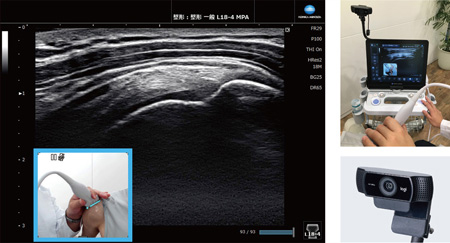

超音波画像とカメラ画像を同時表示Camera Link

カメラで撮影した映像を診断中の超音波画像に重ねて表示。表示した画像は静止画と動画(音声情報も保持可能)で保存できます。後から検査状態を確認する際や,情報共有に便利です。

※オプション機能